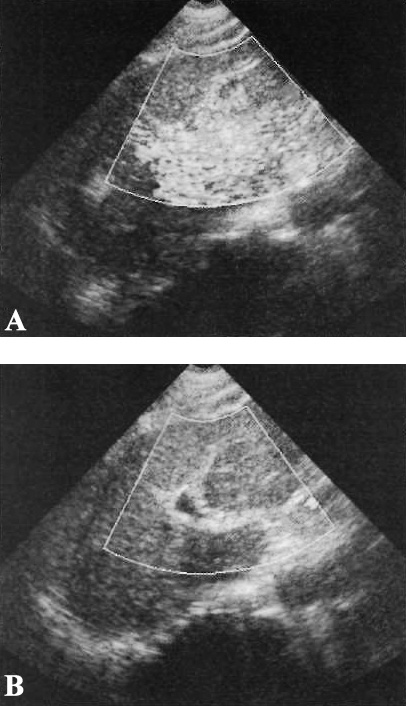

УЗИ брюшной полости: артефакт ложного потока при асците

Фото 5. УЗИ брюшной полости: артефакт ложного потока при асците. А – поперечное изображение в режиме серой шкалы через серповидную связку отмечается анэхогенная жидкость, которая ее окружает. В – цветная допплерография демонстрирует окрашенную жидкость

Артефакт ложного потока позволяет выявить течение жидкости или баллотирование (колебание или смещение анатомического образования в какой-либо полости организма) в местах скопления жидкостей (например, при абсцессе или гематоме, которые могут симулировать объемные образования).